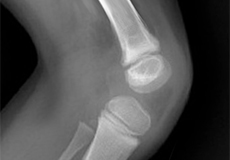

Fractures of the Patella

The patella or kneecap is a small bone present in the front of your knee where the thigh bone meets the shinbone. It provides protection to your knee and attachment to muscles in the front of the thigh.

The knee is a hinge joint made up of two bones, the thighbone (femur) and shinbone (tibia). There are two round knobs at the end of the femur called femoral condyles that articulate with the flat surface of the tibia called the tibial plateau. The tibial plateau on the inside of the leg is called the medial tibial plateau and on the outside of the leg, the lateral tibial plateau.

The two femoral condyles form a groove on the front (anterior) side of the knee called the patellofemoral groove. A small bone called the patella sits in this groove and forms the kneecap. It acts as a shield and protects the knee joint from direct trauma.